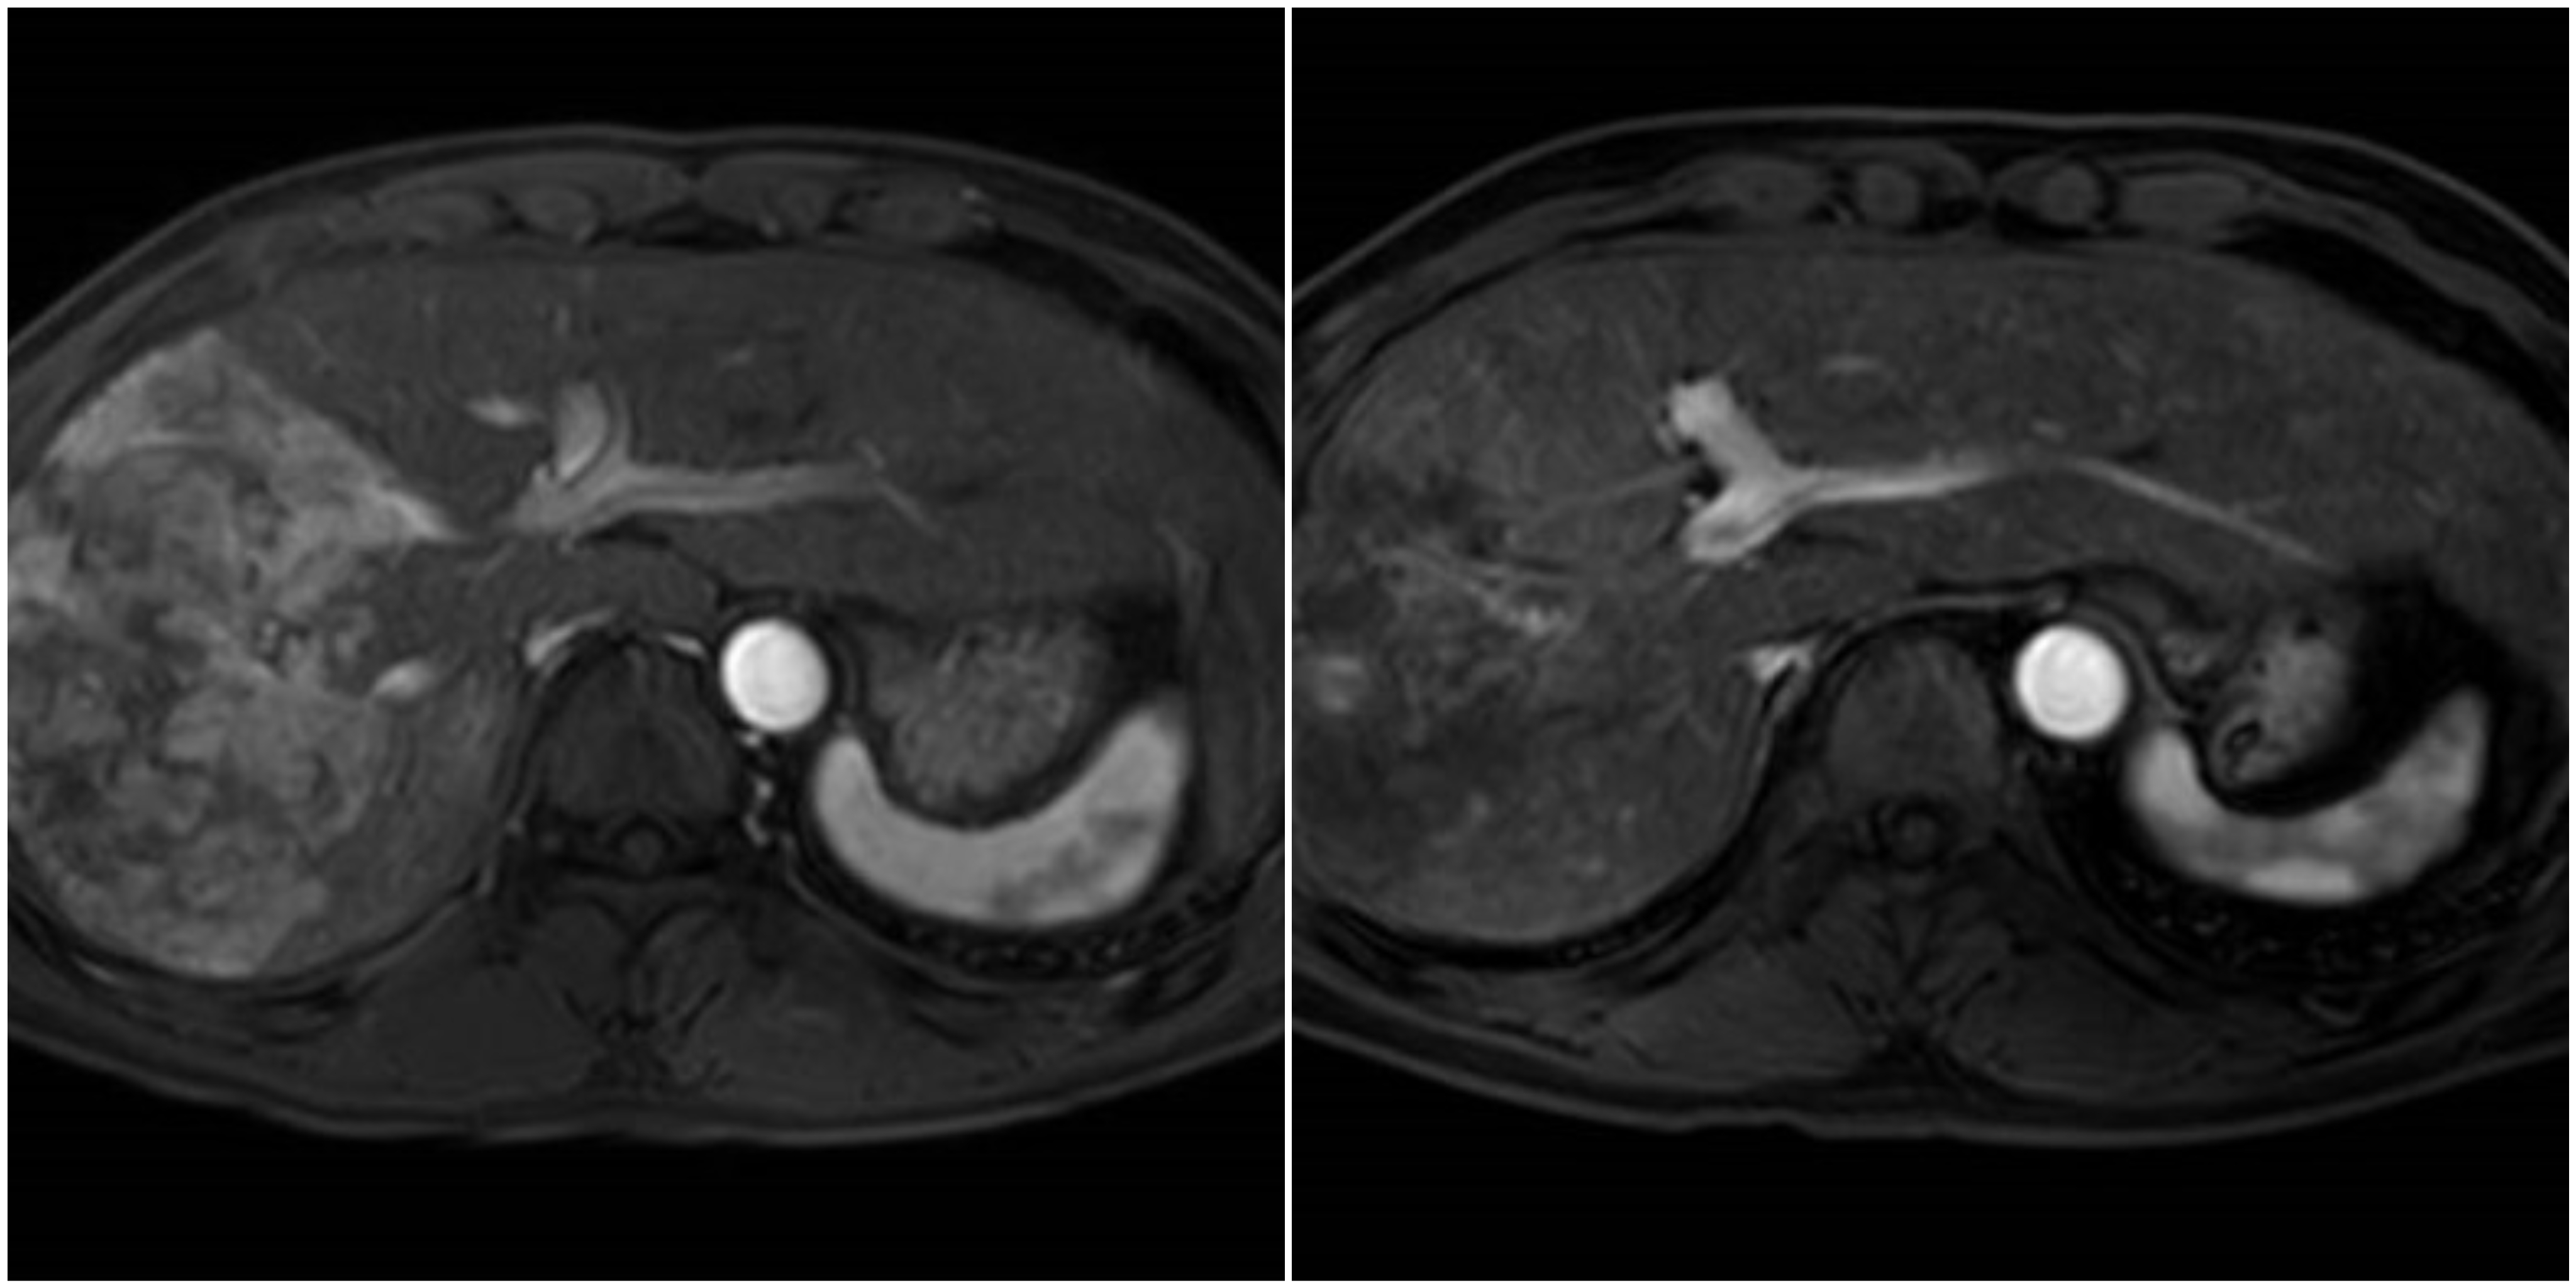

2022.06 病灶最大径11.9cm 2022.12 病灶最大径7.6cm

去年6月15日,湖光院区介入科副主任于士龙带领团队成功为患者实施了经导管肝动脉持续灌注化疗联合肝肿瘤动脉栓塞治疗(HAIC+TAE),经股动脉将PT微导管超选置于肝右动脉,用吡柔比星及超液化碘油+聚乙烯微球栓塞颗粒+明胶海绵颗粒栓塞,栓塞后通过微导管将抗肿瘤药物直接送达肝内肿瘤血管达到治疗目的。术后,患者生命体征平稳,安返病房后通过动脉导管持续泵入化疗药物(奥沙利铂100mg持续泵入3h,氟尿嘧啶3000mg持续泵入45h)。最后辅以抗凝、保肝、水化等对症支持治疗;治疗结束后常规拔管,行局部股动脉加压、包扎止血,患者次日可正常下床行走。首次治疗的成功为患者带来了信心,后期于7月18日、8月22日、9月23日、11月2日序贯接受4次HAIC+TAE治疗,截至春节前夕患者肝内病灶已基本无活性,无需接受局部介入治疗,为预防肝内外复发及转移,给予三氧化二砷全身系统治疗后顺利出院。